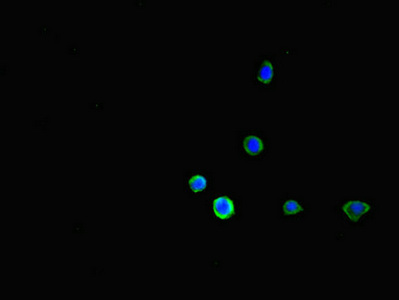

• Immunofluorescent analysis of HepG2 cells using CSB-PA10839A0Rb at dilution of 1:100 and Alexa Fluor 488-congugated AffiniPure Goat Anti-Rabbit IgG(H+L)